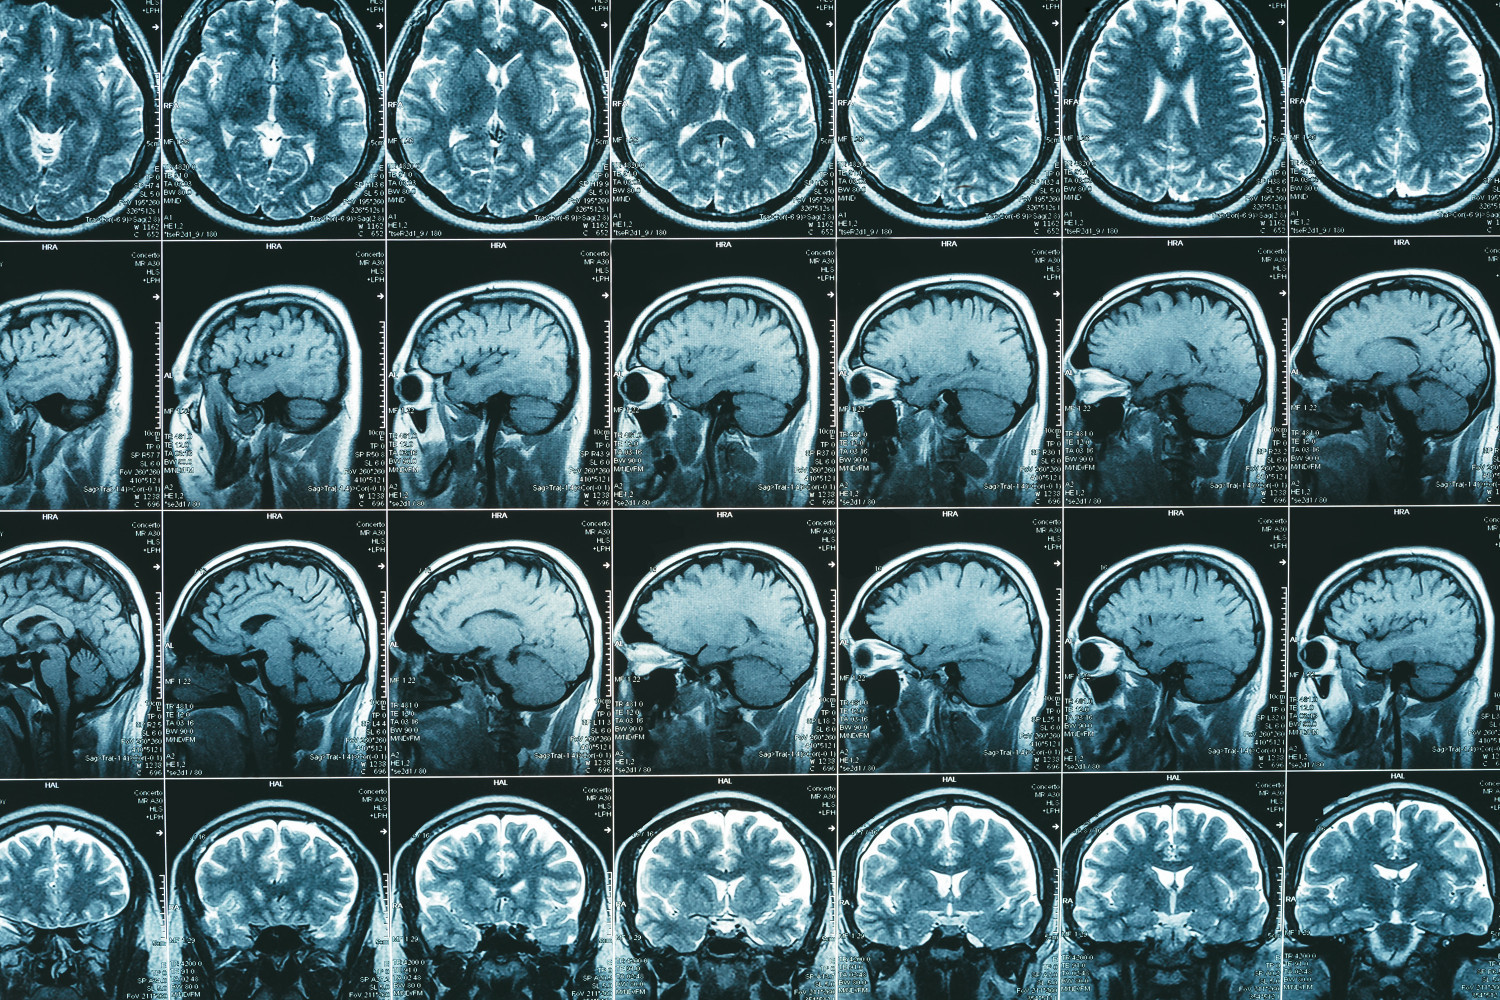

Магнитно-резонансная томография (МРТ) головного и спинного мозга остается наиболее результативным методом диагностики заболевания. Эксперты отметили, что неврит зрительного нерва служит первым проявлением рассеянного склероза в 25—35% случаев при клинически изолированном синдроме. Поэтому следует рассматривать зрительный нерв в качестве «пятой локализации» или пятой анатомической области диссеминации симптомов заболевания в пространстве (DIS), если лучшего объяснения патологии зрительного нерва не существует. При этом минимальный порог диссеминации в пространстве — это наличие хотя бы одного очага хотя бы в двух их пяти топографических областях, включая зрительный нерв.

Эксперты предлагают добавить симптом центральной вены и парамагнитного обода, которые служат маркерами хронических активных поражений на МРТ, в качестве дополнительных инструментов для диагностики рассеянного склероза в определенных ситуациях. Визуализация симптома центральной вены с помощью МРТ может повысить специфичность.